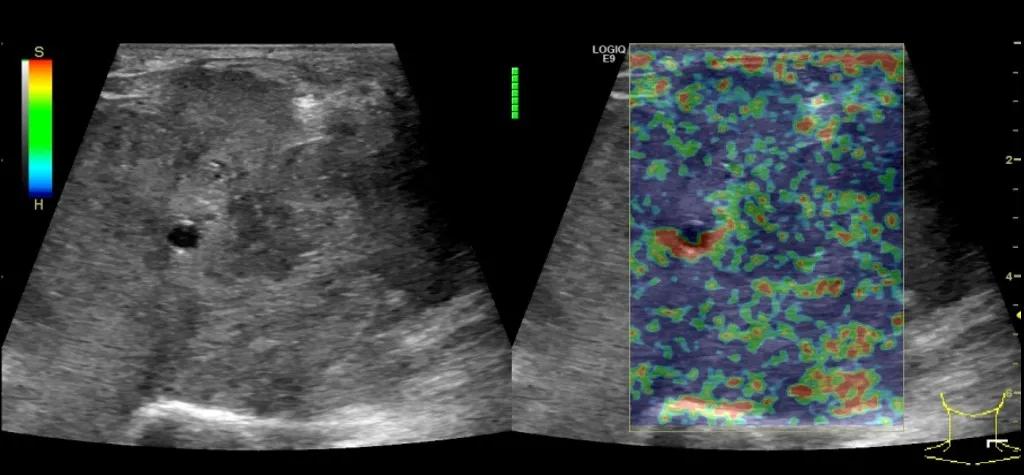

第三例是甲状腺癌患者,双侧甲状腺癌切除术后、碘治疗后一年余效果欠佳,超声显示左颈3区3枚低回声结节,穿刺示甲状腺乳头状癌转移。患者不愿意手术,希望采取局部治疗。对病灶进行液体隔离后采取热消融术,由于淋巴结较小,热消融一分钟左右完全灭活,术后增强影像显示没有脏器充填。

(病例3图例)